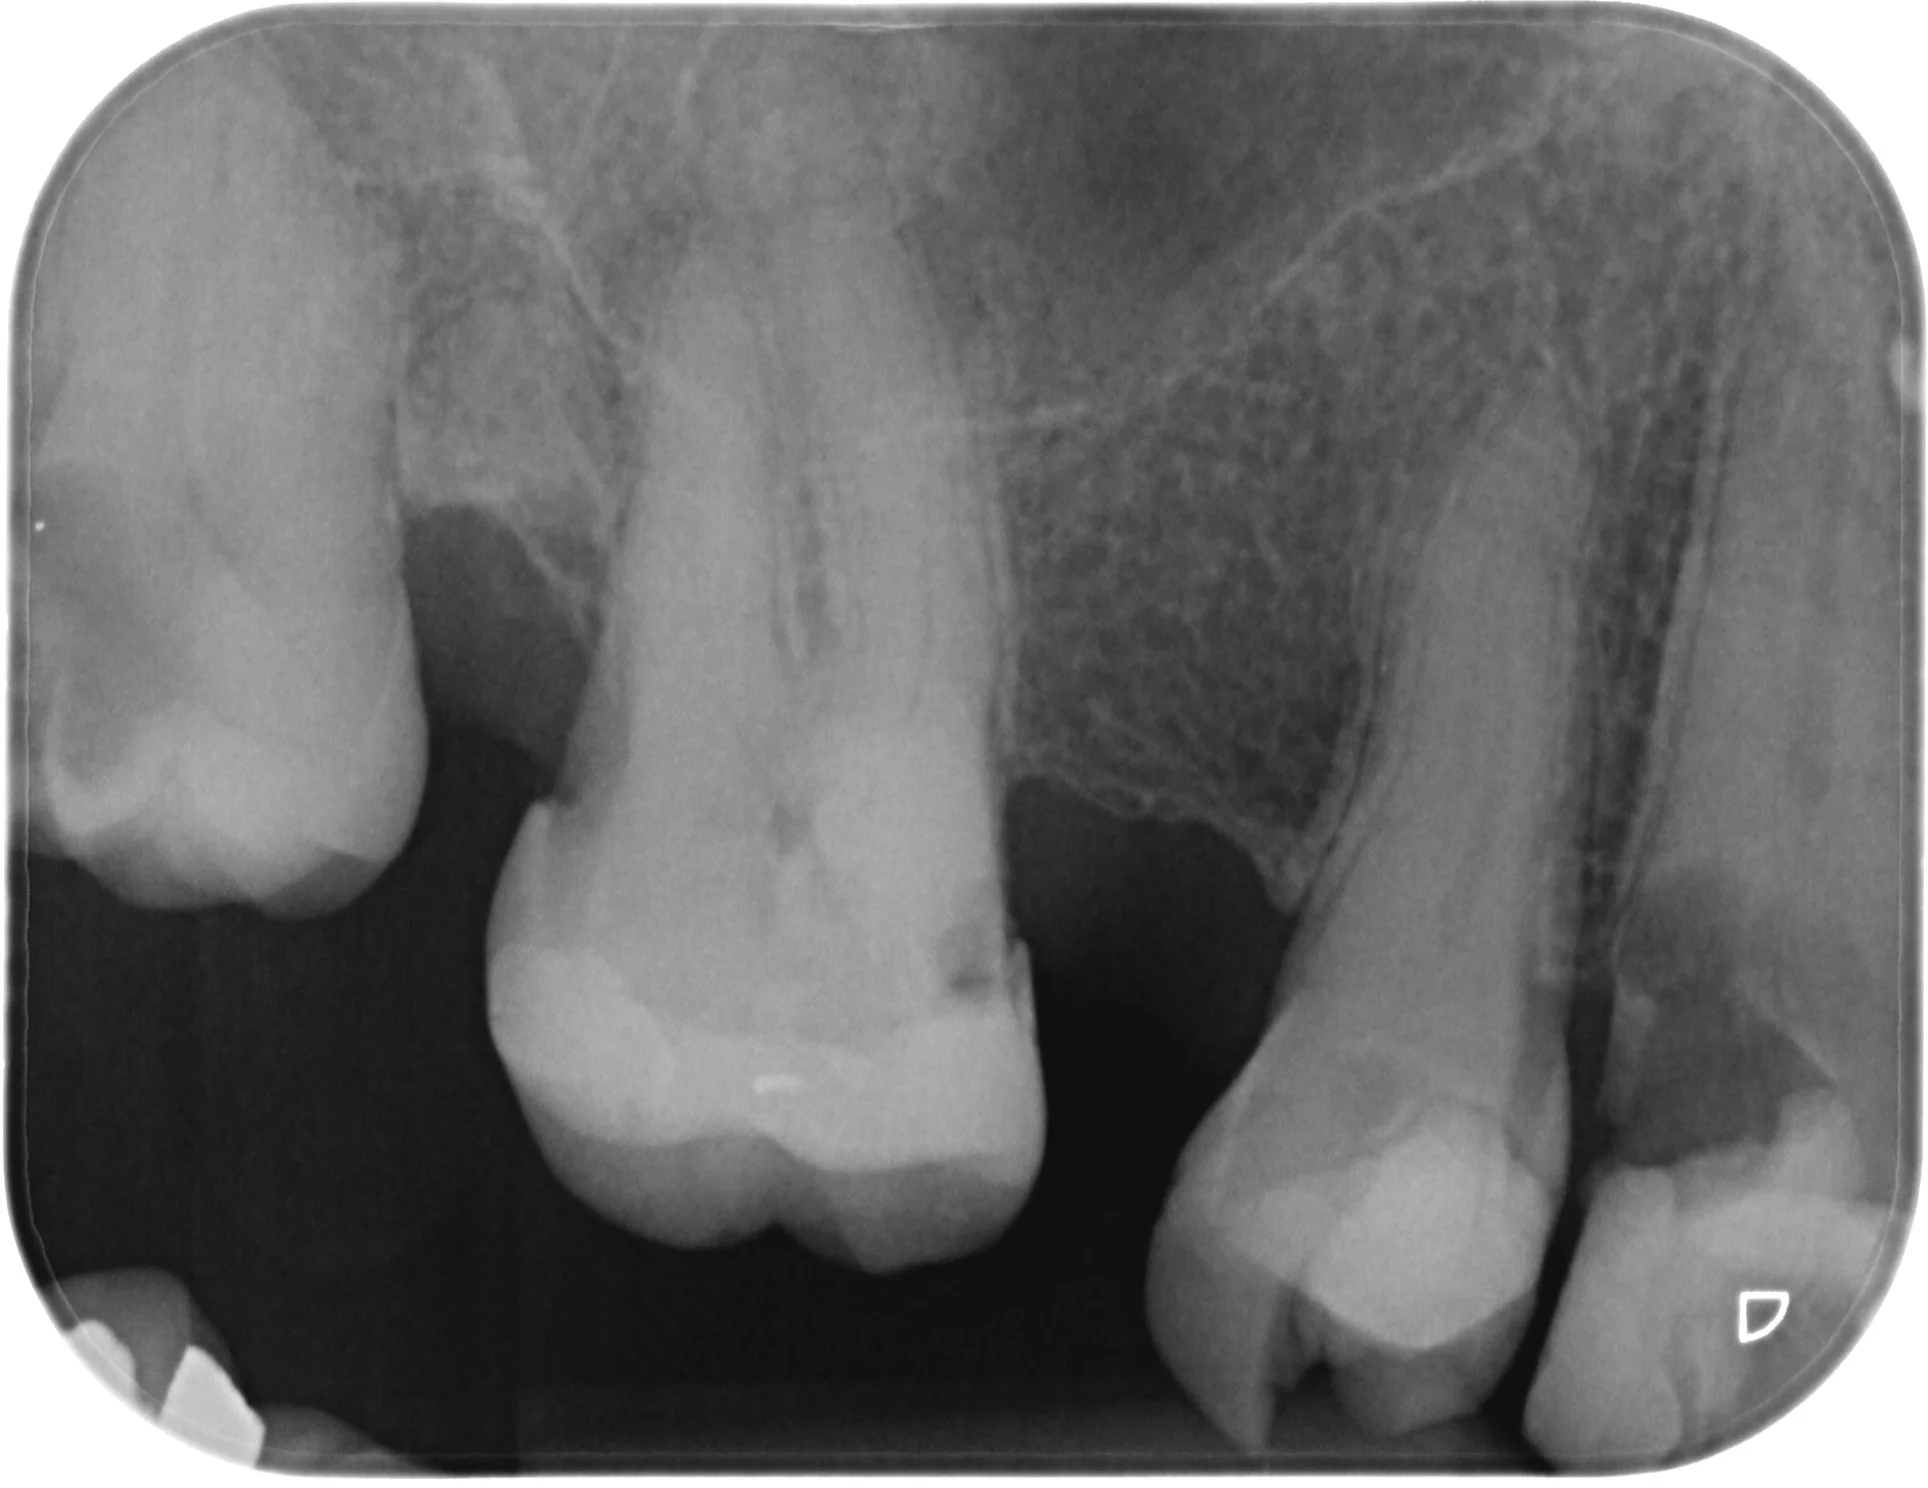

A difficult tooth #16 root canal

This was a fairly difficult tooth #16 root canal I performed recently. The MB2 orifice was very calcified and buried underneath a substantial amount of tertiary dentine. A significant trough of about 2mm depth along the MB groove was needed to uncover the MB2 orifice. The access was also extended fairly mesial to help obtain straight line access into the MB2 canal coronal 1/3.

Note #13 planned for extraction